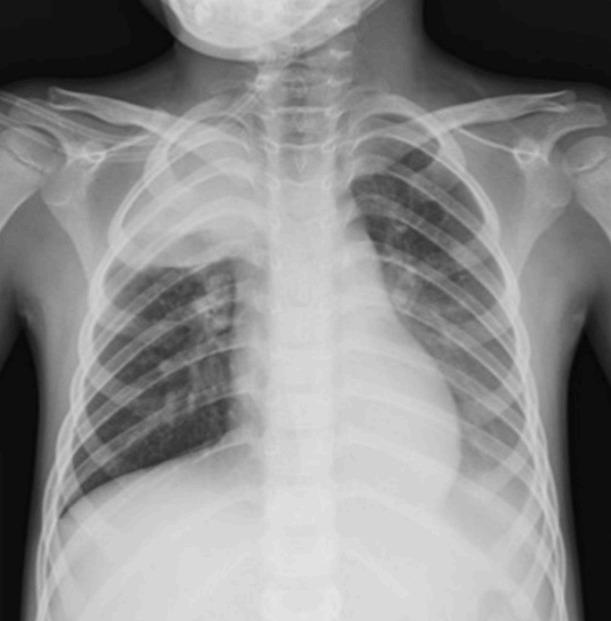

Acute cerebral infarctions are rare in children, however they can occur as a complication of a (MP) infection due to direct invasion, vasculitis, or a hypercoagulable state. We report on the case of a 5-year-old boy who had an extensive stroke in multiple cerebrovascular territories 10 days after the diagnosis of MP infection. Based on the suspicion that the cerebral infarction was associated with a macrolide-resistant MP infection, the patient was treated with levofloxacin, methyl-prednisolone, intravenous immunoglobulin, and enoxaparin. Despite this medical management, cerebral vascular narrowing progressed and a decompressive craniectomy became necessary for the patient's survival. According to laboratory tests, brain magnetic resonance imaging, and clinical manifestations, the cerebral infarction in this case appeared to be due to the combined effects of hypercoagulability and cytokine-induced vascular inflammation.

急性脑梗死在儿童中较为罕见,然而,它可能作为支原体(MP)感染的并发症出现,原因包括直接侵袭、血管炎或高凝状态。我们报告了一例5岁男孩的病例,该男孩在诊断为MP感染10天后,在多个脑血管区域发生了广泛的中风。基于脑梗死与大环内酯耐药MP感染相关的怀疑,该患者接受了左氧氟沙星、甲泼尼龙、静脉注射免疫球蛋白和依诺肝素治疗。尽管采取了这种治疗措施,脑血管狭窄仍在进展,为了患者存活,进行减压颅骨切除术成为必要。根据实验室检查、脑磁共振成像和临床表现,该病例中的脑梗死似乎是由于高凝状态和细胞因子诱导的血管炎症的联合作用所致。